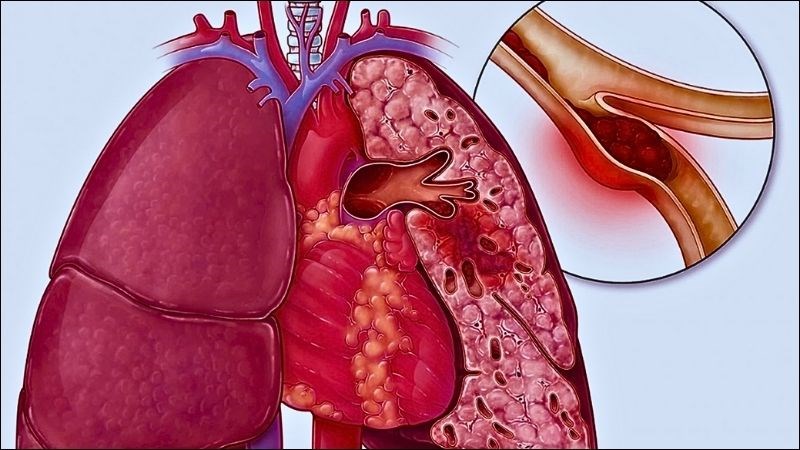

Bệnh tràn dịch màng phổi hay còn gọi hội chứng tràn dịch màng phổi, là tình trạng tích tụ chất lỏng (có thể là dịch hoặc máu) trong khoang trống giữa 2 màng phổi (màng phổi thành và màng phổi tạng) vượt quá mức cho phép. [1]

Tràn dịch màng phổi là tình trạng một lượng lớn chất lỏng tích tụ trong các mô và khoang trong phổi

Thuyên tắc phổi

Đây là tình trạng tắc nghẽn động mạch và mao mạch phổi, ảnh hưởng đến quá trình trao đổi khí và lưu thông máu. Áp lực trong mạch máu tăng cao làm ứ đọng chất lỏng tại khoang màng phổi gây tràn dịch màng phổi.

Thuyên tắc phổi gây làm tắc nghẽn quá trình trao đổi khí và lưu thông máu tại phổi